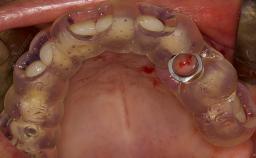

- describe the surgical treatment concept and steps for the lateral SFE technique and assess the prognosis of this procedure